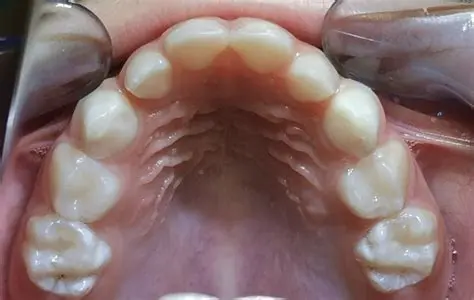

O Uso Prolongado da Chupeta